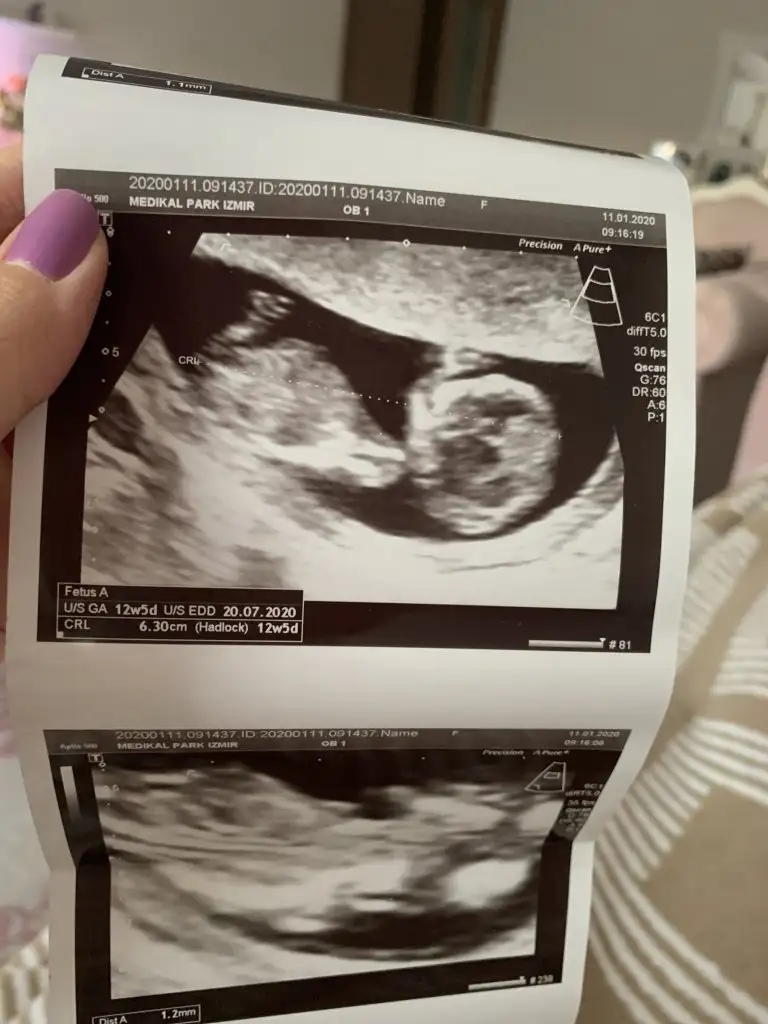

Arada kaldım yüzde altmış kız yüzde kırk erkek

Teşekkür ederim. Hayırlısı sağlıklı olsun inşallah. Doktora da sordum da bakti epey hic fikir yürütemiyorum dedi hangi resme göre yorumladınız birinde sırtı dönük gibi. Yanılıyor muyum?Arada kaldım yüzde altmış kız yüzde kırk erkek